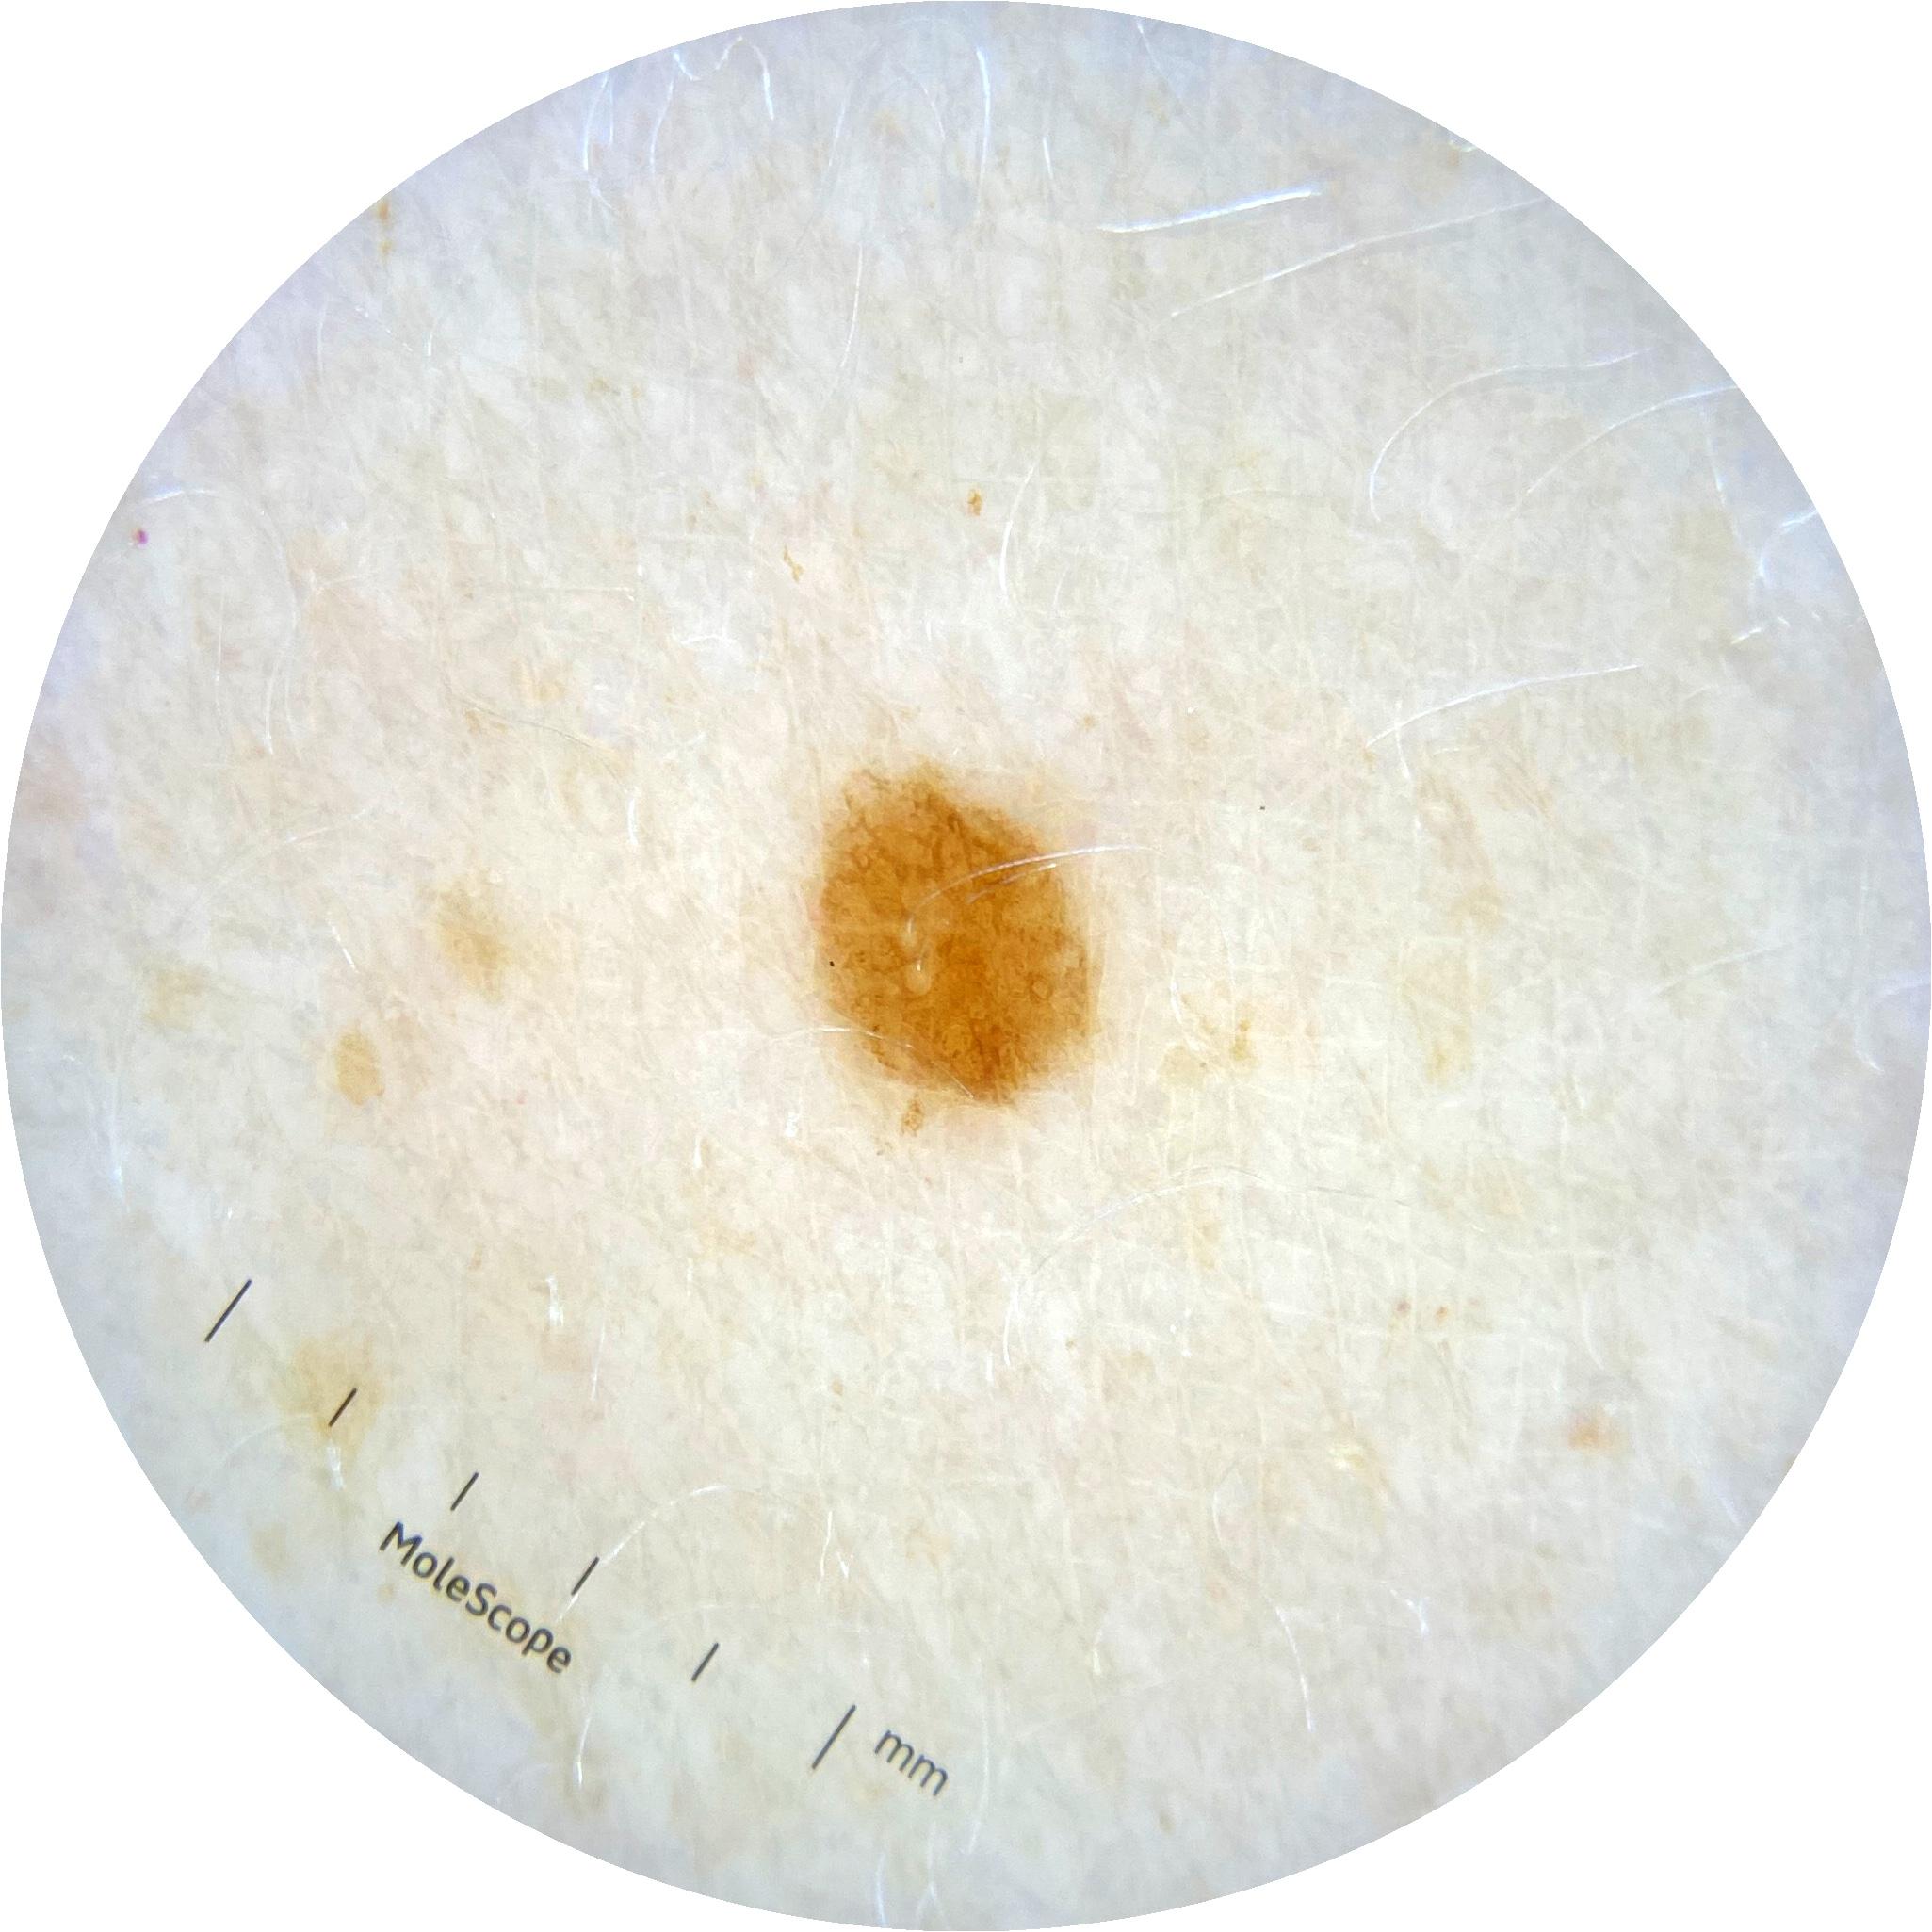

ISIC_2261268

acquisition_day 307

age_approx 50

anatom_site_1 Trunk

anatom_site_2 Posterior trunk

anatom_site_general posterior torso

diagnosis_1 Benign

diagnosis_confirm_type single image expert consensus

image_type dermoscopic